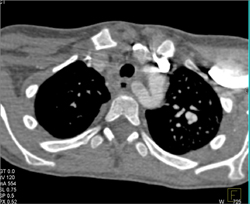

Diagnosis

Type A Dissection